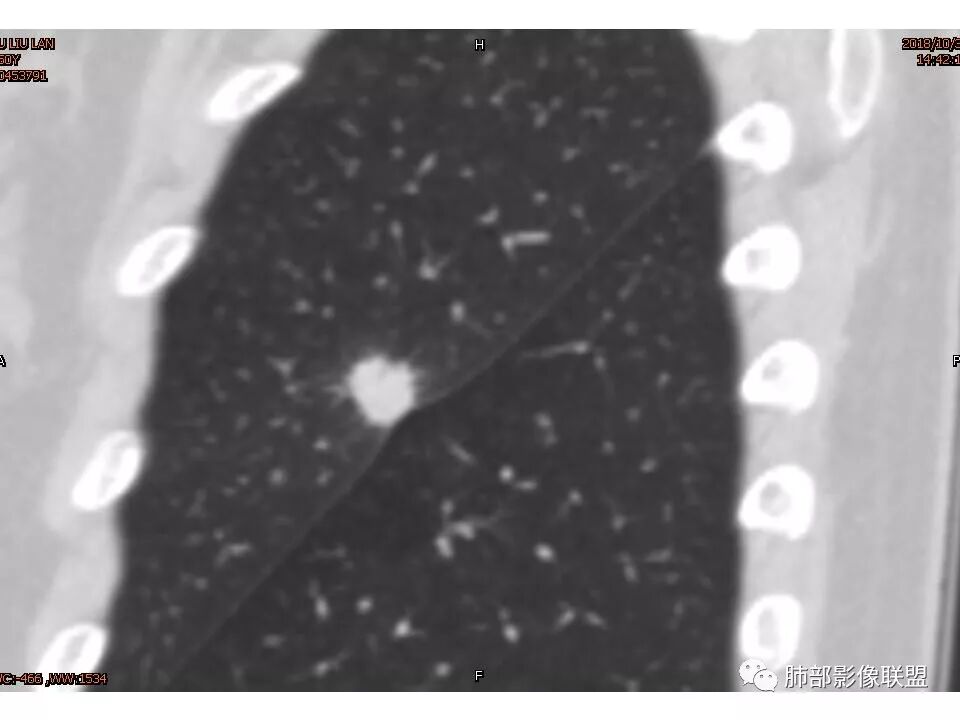

左肺上叶后段病灶,有毛刺,有胸膜牵拉,有血管滋养,好像还可以看见内部空泡,深分叶,边界比较清楚,考虑恶性肿瘤。

左肺上叶实性不规则结节,有深分叶,短毛刺,有切迹,有血管集束,有胸膜牵拉,常规考虑恶性,鉴别炎性结节

女性,左上肺实性结节,有毛刺,有血管进入,边缘彭隆,月牙铲,深分叶,边界比较清楚,胸膜牵拉,考虑腺癌。

1.胸膜下略不规则实性密度结节影,孤立,缺乏典型深分叶,可见淡薄边界模糊磨玻璃晕,可见相对细长软毛刺。

2.如南边老师分析,病灶缺乏边缘膨隆优势,甚至部分平直内收。

3.病灶收缩力不强,整体强化程度不显著。

4.综上,病灶更符合炎性,如隐球菌感染等,而不大符合肺腺癌。具体到机化性肺炎略有些出乎预料。